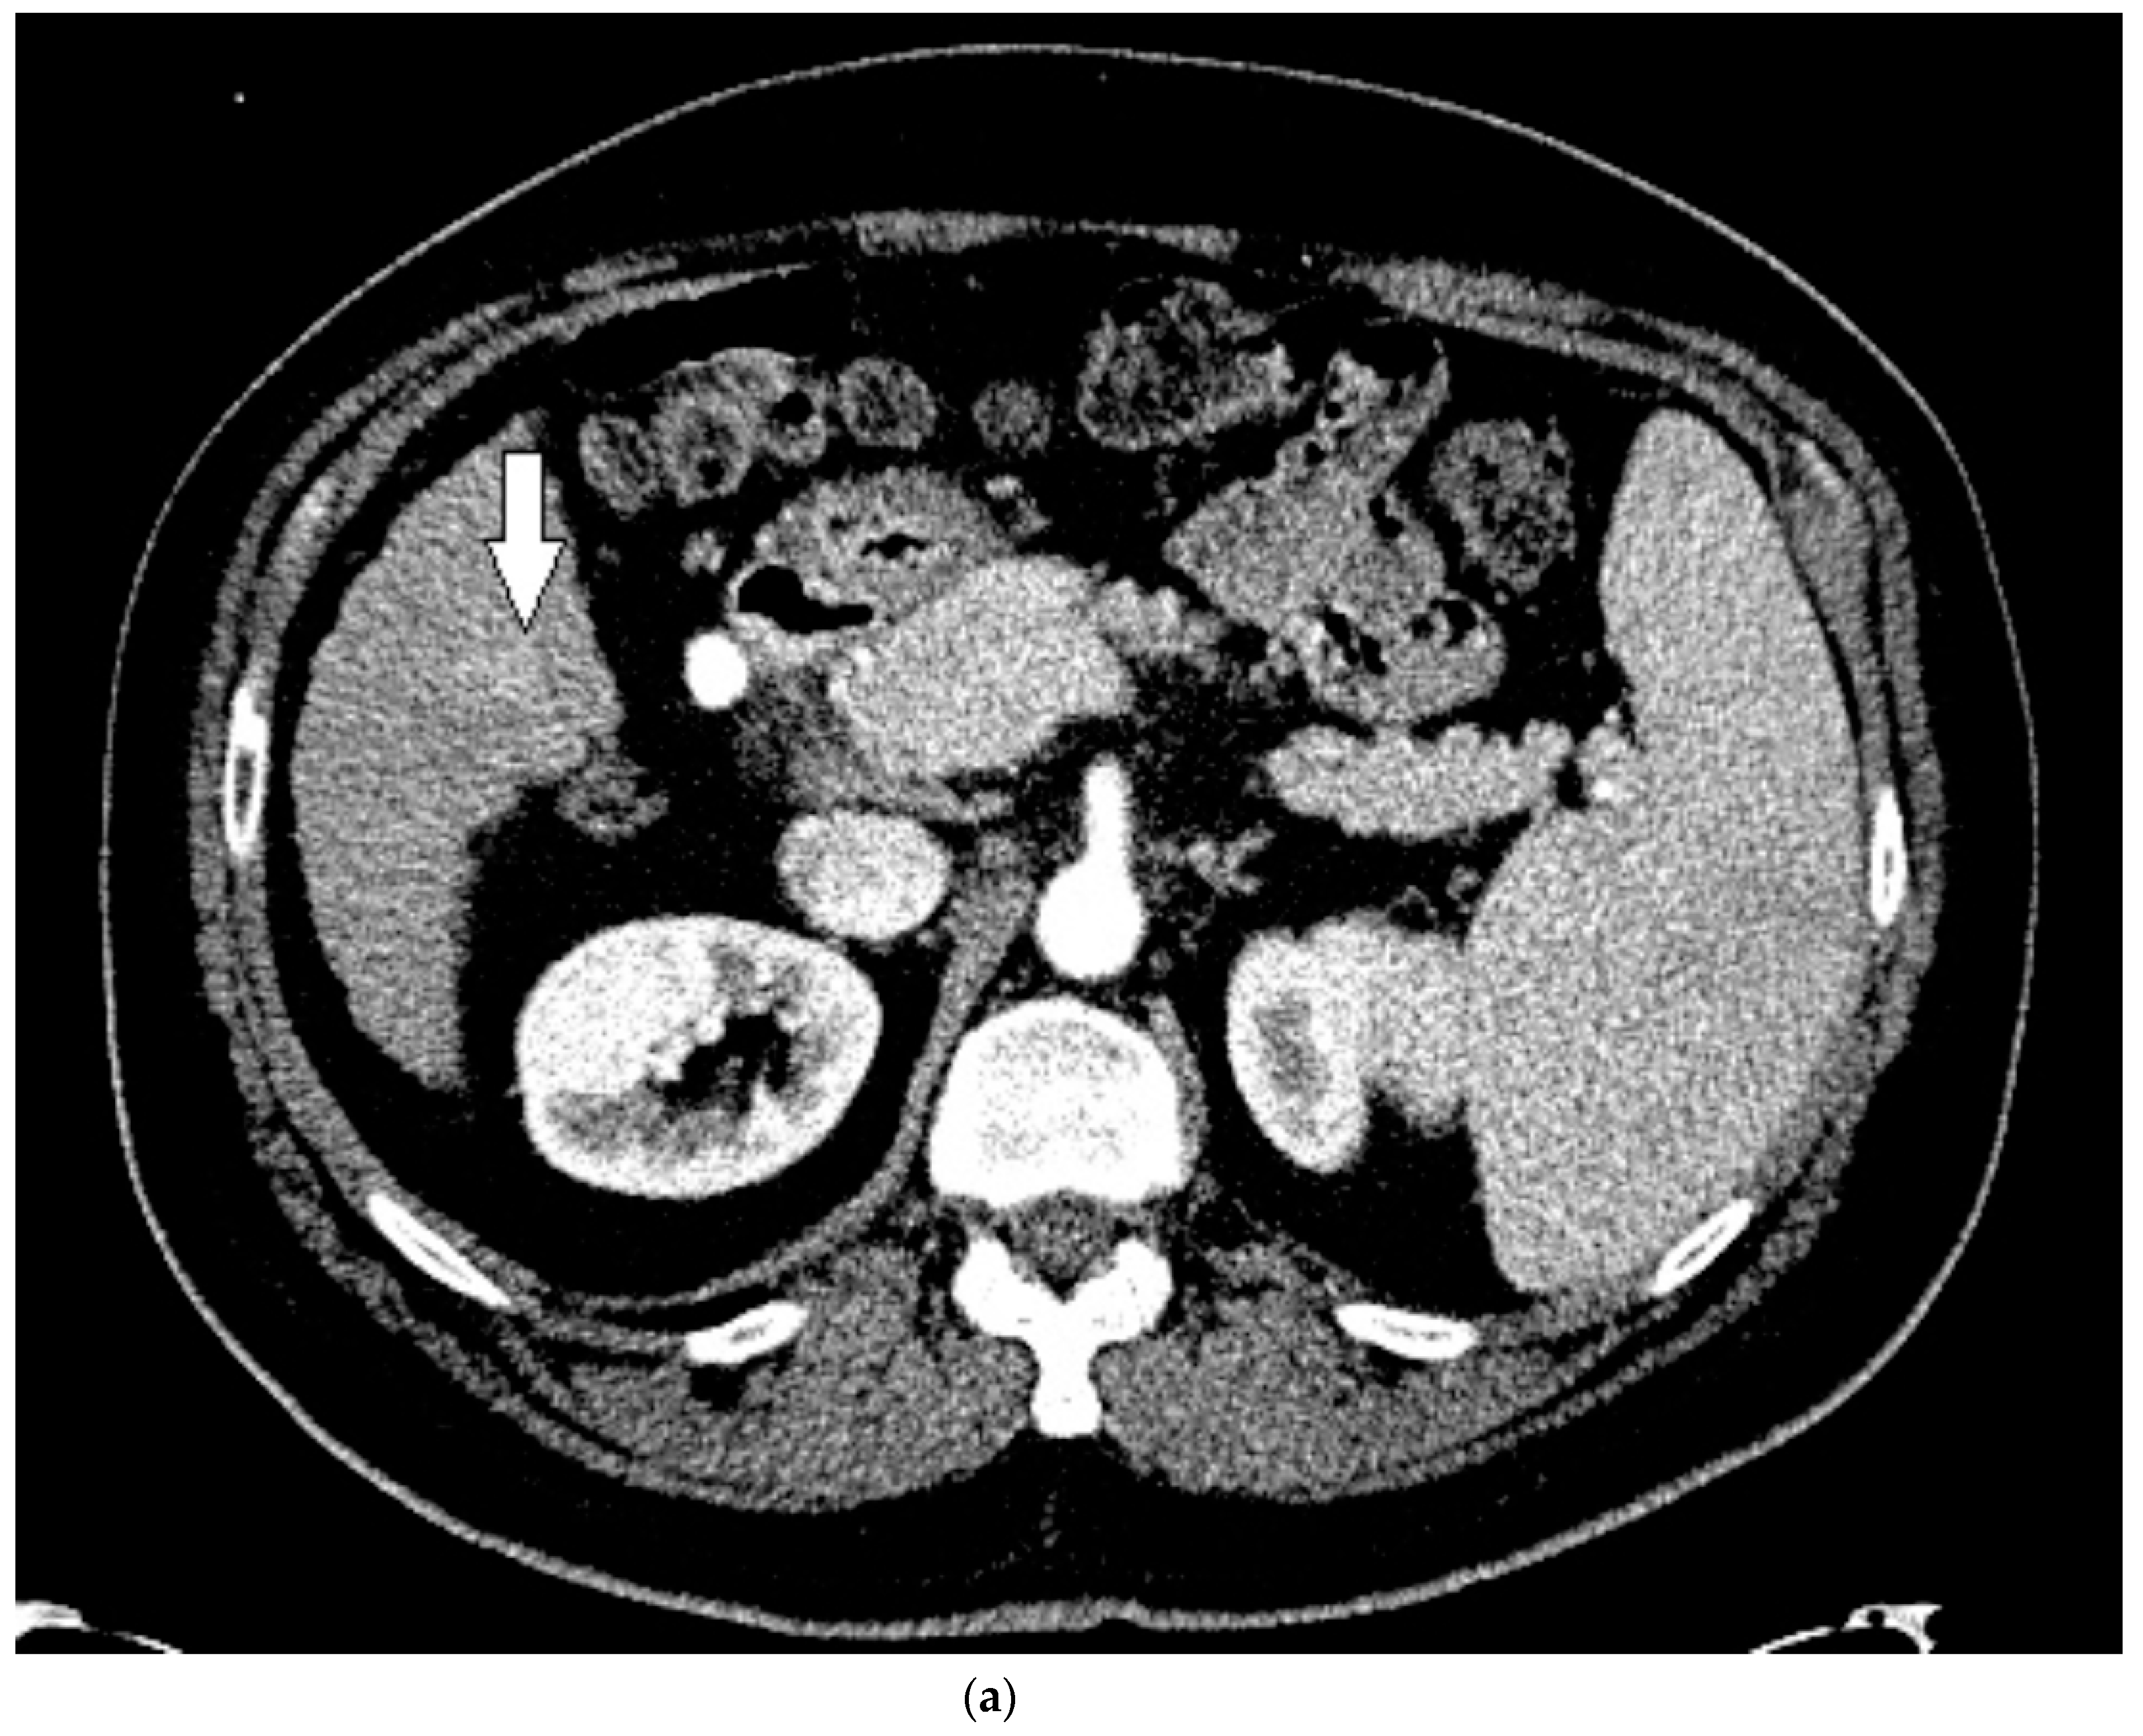

3.3. Case 3